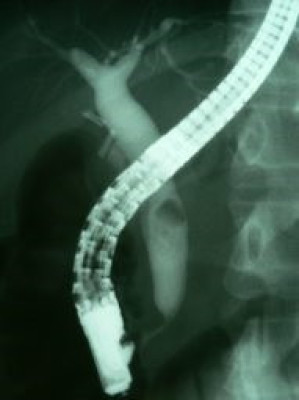

Coledocolitiasis con antecedente de colecistectomía por laparoscopía

Envíado por Dr. Carlos Miguel Zavaleta Consuegra